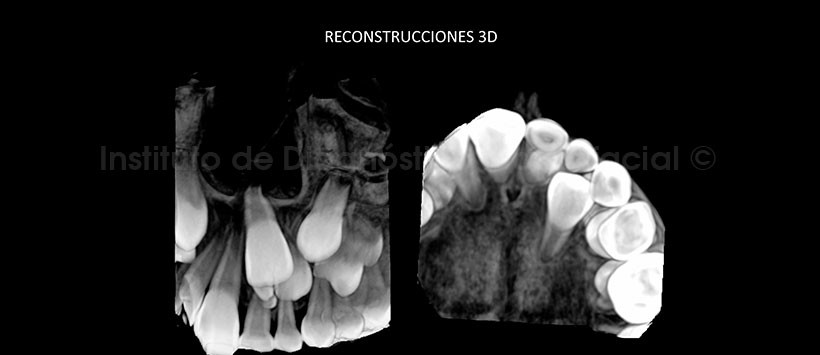

En las reconstrucciones 3D, se evidencia claramente lo antes descrito y su relación con estructuras adyacentes, con lo que se confirma la presunción diagnóstica de odontoma compuesto. (Figuras 5 y 6)